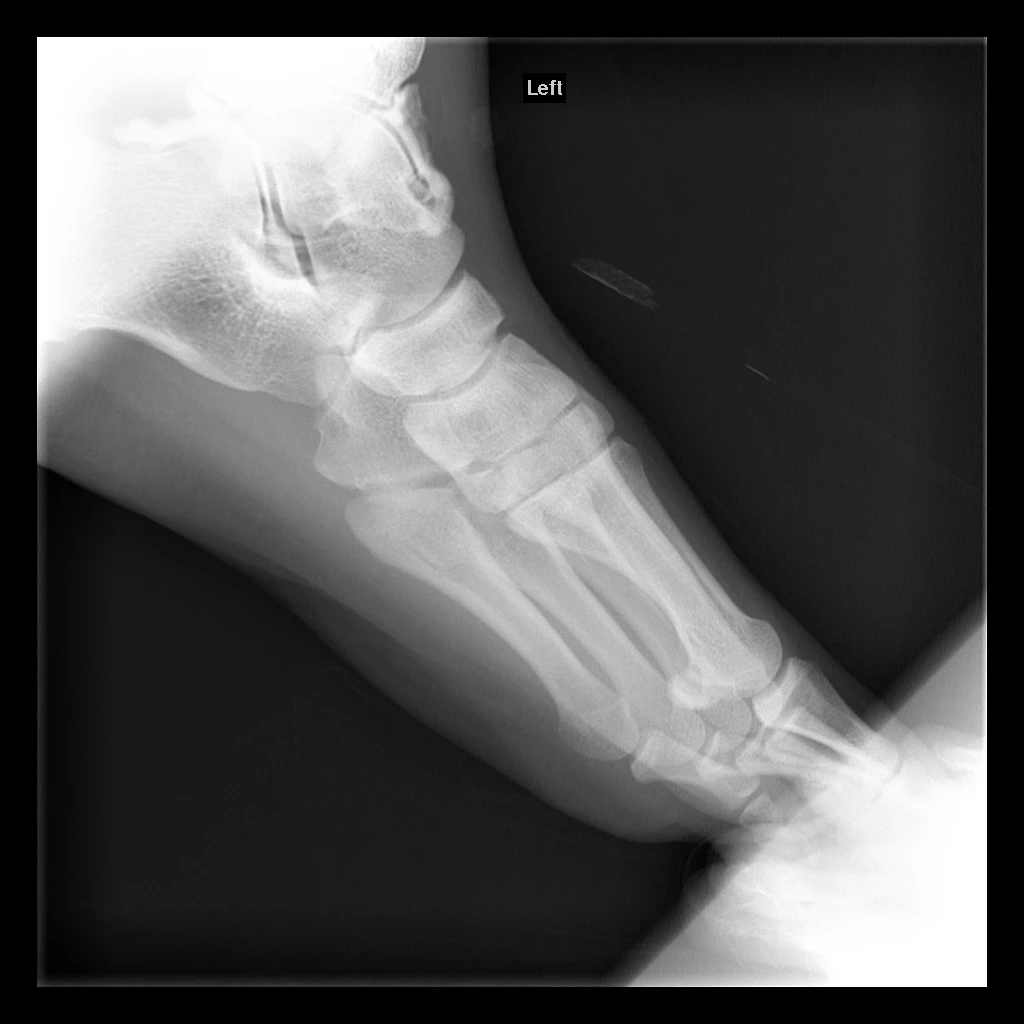

CT Scan Review

Dr. Choung reviews the CT scan and explains the current state of the ankle:

• Anatomy: The medial gutter (inside portion) of the left ankle is where the cartilage injury and surgery occurred. The lateral gutter (outside) is healthy for comparison

• Osteotomy site: The medial malleolus was cut to access the joint during surgery (can't reach from the front). Two screws were placed. Some irregularity visible at this bone cut

• Bone spurs: Small spurs have developed at the front of the joint, possibly from the osteotomy healing or imperfect cartilage graft match with the tibia

• Graft incorporation: The cartilage graft incorporated well overall and has blood supply, but because it's a donor graft, it's not perfect — the bone has some mechanical inferiority

• Pressure mismatch: Hard to get a perfect anatomical match from a donor. Even a small mismatch causes uneven pressure distribution, which damages the cartilage receiving excess pressure

• Cysts: Multiple small cysts have developed throughout the graft from this pressure damage. Visible throughout various portions of the graft

• Cartilage surface: The front part of the graft's bony border is still intact. The back portion shows discontinuity — areas where cysts have broken through to the cartilage surface

• Bone wearing: The bone substance that supports the cartilage has worn down since surgery 14-15 years ago

• Possible pain sources: Could be any combination of: cartilage wearing, cysts, or bone spurs — difficult to determine which is the primary cause

• Recommended imaging: An MRI with metal suppression would be helpful to fully evaluate the cartilage (CT can't assess cartilage directly)